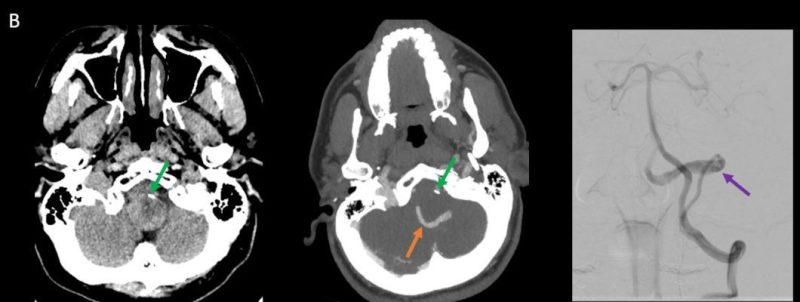

- B. Kontrastsız BT incelemede heterojen dansitede, perferinde kaba kalsifikasyon gösteren kitle lezyonu (ok), BT anjiografi MIP aksiyal kesitte yılan gibi eksantrik bir açık damar görülmektedir (ok). Sağ posterior inferior serebellar arterden (PICA) doluş gösteren tortiyoze dilate vasküler yapı (ok) DSA’ da demonstre edilmiş.

- BT anjiyografi (BTA) ile anevrizma içindeki patent, serpantin damar kanalı ve anevrizmanın besleyici damarları daha net bir şekilde görüntülenebilir.

- Serpantin anevrizmaların tanısında altın standart olarak kabul edilir.

- Anevrizmanın şeklini, giriş ve çıkış noktalarınıen net şekilde gösterir.

- DSA’da anevrizma içindeki tortuöz damar kanalının morfolojisi, bir simite (“pretzel işareti”) benzetilmiştir. Bu bulgu, anevrizmanın dinamik yapısını ve içindeki kan akışınıgörselleştirmek için kritik bir bulgudur.